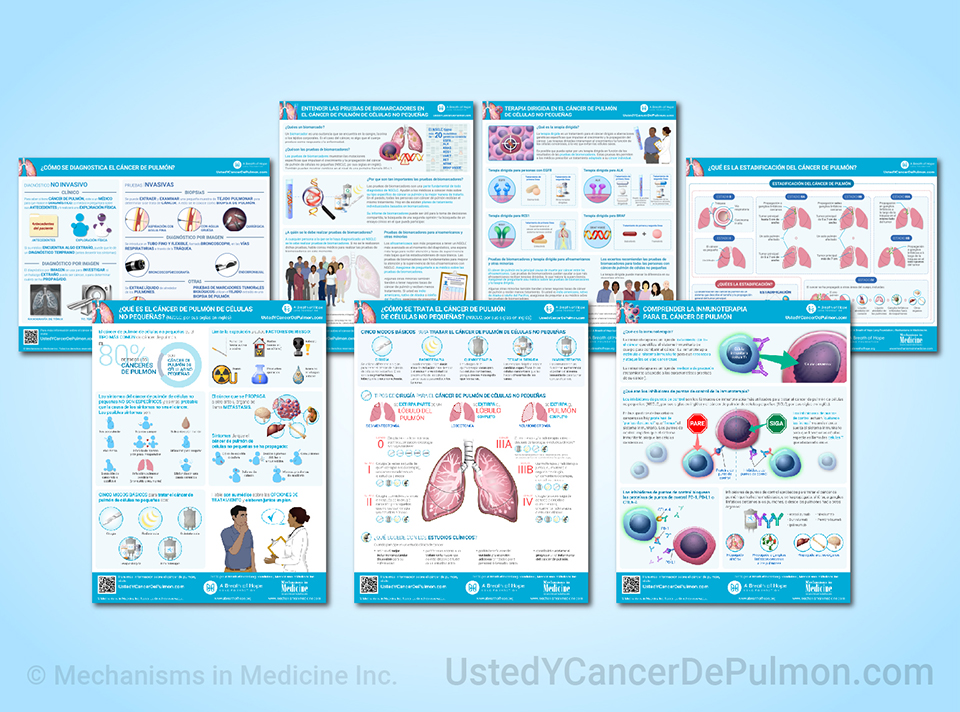

Mejore su comprensión de cáncer de pulmón con nuestras infografías descargables gratuitas.

Este sitio web es parte de la serie Animated Patient™ desarrollada por Mechanisms in Medicine Inc., para proporcionar formatos de aprendizaje con abundante contenido visual para pacientes, a fin de mejorar su comprensión, tomar decisiones informadas y trabajar conjuntamente con sus profesionales médicos para obtener resultados óptimos.